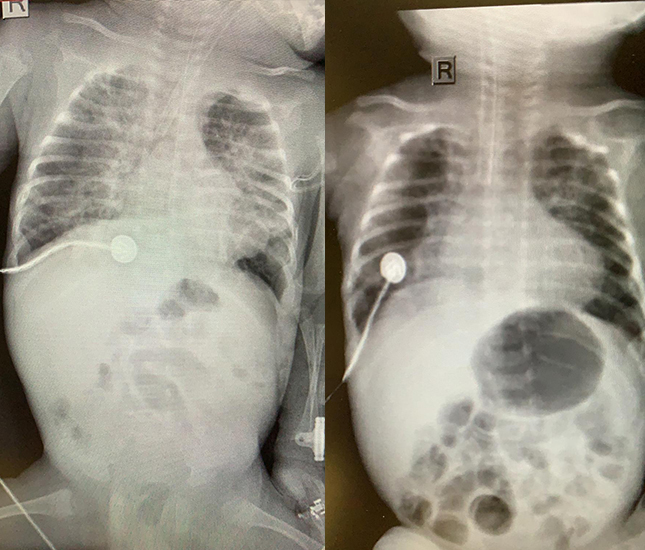

(poze: inainte si dupa terapia cu celule stem)

Dupa administrarea primei doze, s--a constatat o usoara imbunatatire a starii generale si a parametrilor inflamatori, cu toate acestea, a fost in continuare necesar sa se ofere suport ventilator, pentru ca bebelusul sa poata respira. Conform protocolului stabilit initial, la trei saptamani de la administrarea primei doze, s-a administrat o a doua doza cu o concentratie mai mare. Dupa administrarea celei de a doua doze, evolutia a fost spectaculoasa, atat din punct de vedere al examinarii clinice, cat si al rezultatelor paraclinice. Nivelul citokinelor inflamatorii a scazut spectaculos, saturatia de oxigen s-a imbunatatit, bebelusul nu a mai avut nevoie de suport respirator.

(poza: inainte si a doua zi dupa a doua tura de terapie cu celule stem)